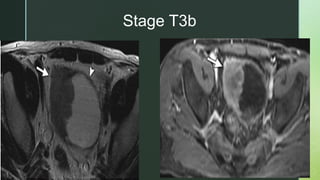

 Stage T3b: A bladder wall lesion with an irregular, shaggy outer

border and streaky areas of the same signal intensity as the tumor

in perivesical fat.

Stage T3b

z  Stage Taor T1: An intact, low T2 signal intensity muscle layer at the base of the tumor is indicative of nonmuscle invasive bladder tumor.  Stage T2: Muscle invasive tumor is suggested when the normal low T2 signal of bladder wall muscle is interrupted by intermediate T2 tumor signal.  Stage T3a (microscopic perivesical invasion) diagnosis is difficult.  Stage T3b: A bladder wall lesion with an irregular, shaggy outer border and streaky areas of the same signal intensity as the tumor in perivesical fat.

• #38 Axial T2 Arrow = extravesical mass of intermediate signal Arrowhead = normal low signal of detrusor muscle. Axial T1 + C FS (60sec) the extravesical enhancing mass (arrow).